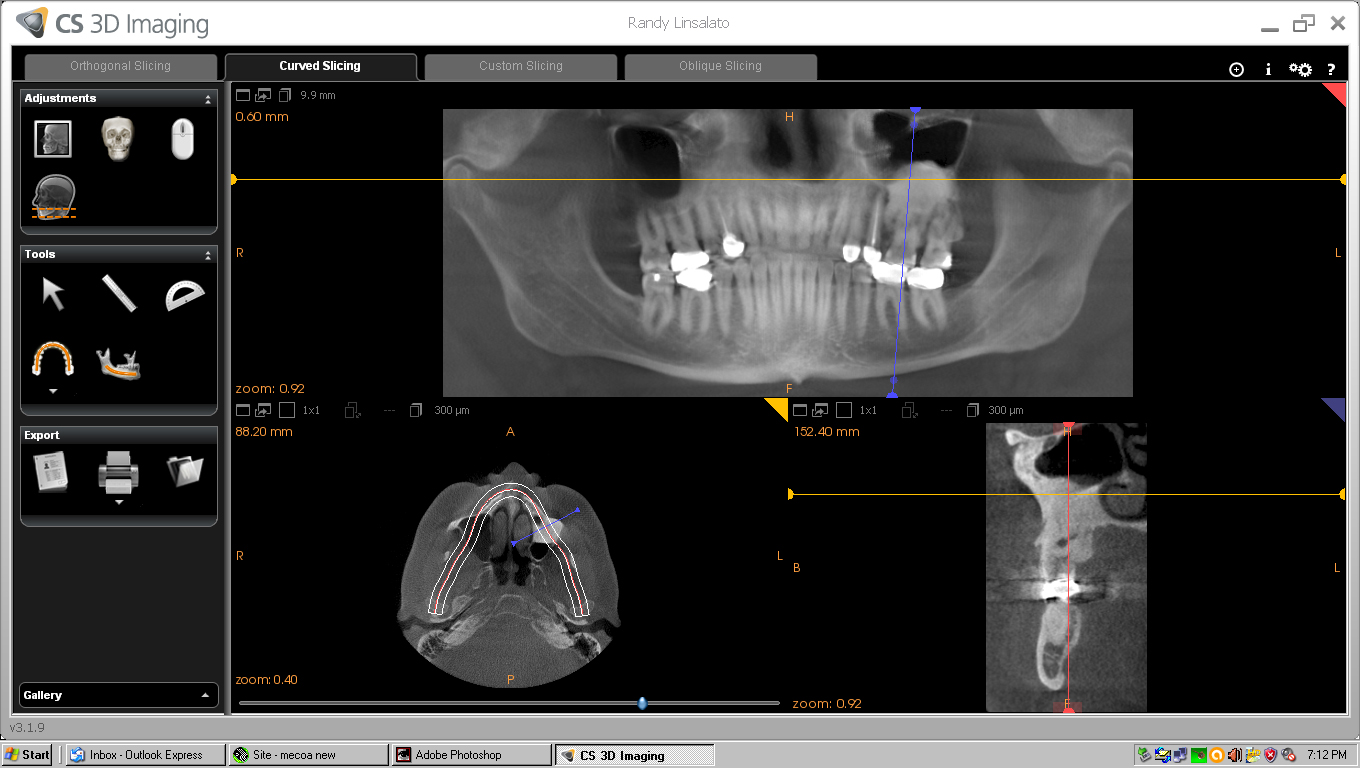

Bone loss in post treatment CT below

Nov/Dec 2013 below

This comparison shows 14 and 15 taken by Fuentes prior to treatment 5-2012 on the left and 9-2016 on the right. Significant bone loss